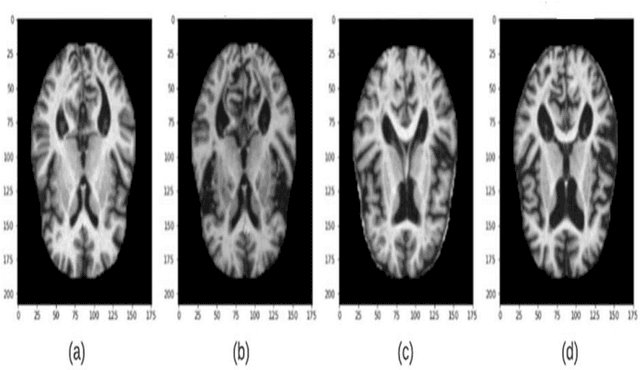

Abstract:Objective: This paper presents an Alzheimer's disease (AD) detection method based on learning structural similarity between Magnetic Resonance Images (MRIs) and representing this similarity as a graph. Methods: We construct the similarity graph using embedded features of the input image (i.e., Non-Demented (ND), Very Mild Demented (VMD), Mild Demented (MD), and Moderated Demented (MDTD)). We experiment and compare different dimension-reduction and clustering algorithms to construct the best similarity graph to capture the similarity between the same class images using the cosine distance as a similarity measure. We utilize the similarity graph to present (sample) the training data to a convolutional neural network (CNN). We use the similarity graph as a regularizer in the loss function of a CNN model to minimize the distance between the input images and their k-nearest neighbours in the similarity graph while minimizing the categorical cross-entropy loss between the training image predictions and the actual image class labels. Results: We conduct extensive experiments with several pre-trained CNN models and compare the results to other recent methods. Conclusion: Our method achieves superior performance on the testing dataset (accuracy = 0.986, area under receiver operating characteristics curve = 0.998, F1 measure = 0.987). Significance: The classification results show an improvement in the prediction accuracy compared to the other methods. We release all the code used in our experiments to encourage reproducible research in this area